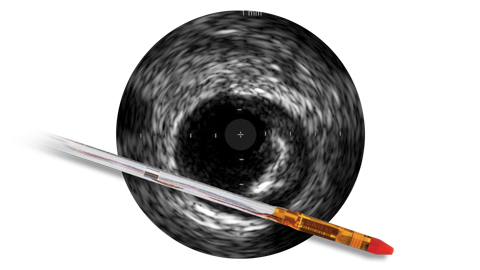

Между тем, использование ВСУЗИ помогает получить более четкую картину и улучшить результаты лечения пациента за счет планирования стентирования на основе данных и оптимизации стента после его установки1.

Использование ВСУЗИ ассоциировано с меньшим объемом контрастного вещества: 20 мл по сравнению с 64,5 мл, p<0,001, n=83 пациента, участвующих в рандомизированных исследованиях (ЧКВ с применением ВСУЗИ или ангиографии)12. ВСУЗИ помогает определить: • Патологию на неоднозначном участке с целью оптимизации стратегии лечения • Эффективность использования устройства без дополнительного облучения и ввода контрастного вещества

При использовании ВСУЗИ в качестве методики контроля пациентам вводился меньший объем контрастного вещества: 20 мл по сравнению с 64,5 мл, p<0,001, n=83 пациента, участвующих в рандомизированных исследованиях (ЧКВ с применением ВСУЗИ или ангиографии).12 ВСУЗИ помогает определить: • Патологию на неоднозначном участке с целью оптимизации стратегии лечения • Эффективность использования устройства без дополнительного облучения и ввода контрастного вещества